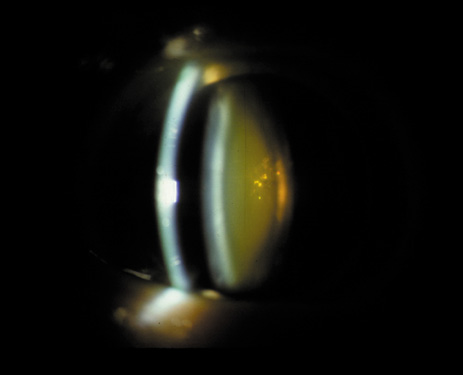

One can examine this type of cataract with direct illumination, using the narrow and broad beams of the slit-lamp to show the characteristic granular inner surface immediately in front of the posterior capsule (Fig. 13). The problem with this technique, however, is that patients may not tolerate any prolonged direct illumination because of the glare. Retroillumination is therefore more useful for revealing the outline of the opacity, since it is usually seen as an “island” in the center of the posterior capsule, which is further highlighted by the shadow cast by the opacities.33 However, in the early stages of this type of cataract, the dust-like particles that might be noticeable in the central posterior subcapsular area with direct illumination disappear or are difficult to see with retroillumination (Fig. 14). Eventually this “dusting” becomes dense enough to cast a shadow and thus appear on retroillumination. The smooth orange background of the fundus helps to highlight the rough, irregular pseudopodia-like edges of the central opacity. In advanced stages, the PSC may become a thick, calcified plaque (Fig. 15). During surgery, excessively vigorous scraping or vacuuming of the calcified opacity can lead to rupture of the posterior capsule. Usually, small remnants that are left behind after surgery are reabsorbed and do not interfere with vision; otherwise, they are easily treated with a neodymium : yttrium (Nd:YAG) aluminum garnet laser. Pathologic evidence suggests that most PSCs result from the migration of bow region cells into the potential space (along with accumulated cellular debris) between the posterior capsule and the cortex.34–36

Fig. 13. Direct slit-lamp illumination of a PSC, showing an irregular granular surface in front of the posterior capsule.

Fig. 14. A PSC, showing vacuoles and dust-like material in the potential space between the posterior cortex and the capsule.